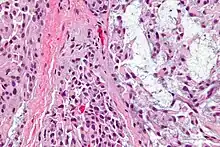

| Micrograph of a myoepithelioma. H&E stain. | |

The myoepithelial cells may be spindled, plasmacytoid, eithelioid or clear. Tubules or epithelium are absent, or present in a small amount (<5%) by definition. Tumours with myoepithelial cells and a large amount of tubules are classified as pleomorphic adenomas (which must also contain the characteristic chondromyxoid stroma, which is normally absent in myoepithelioma).